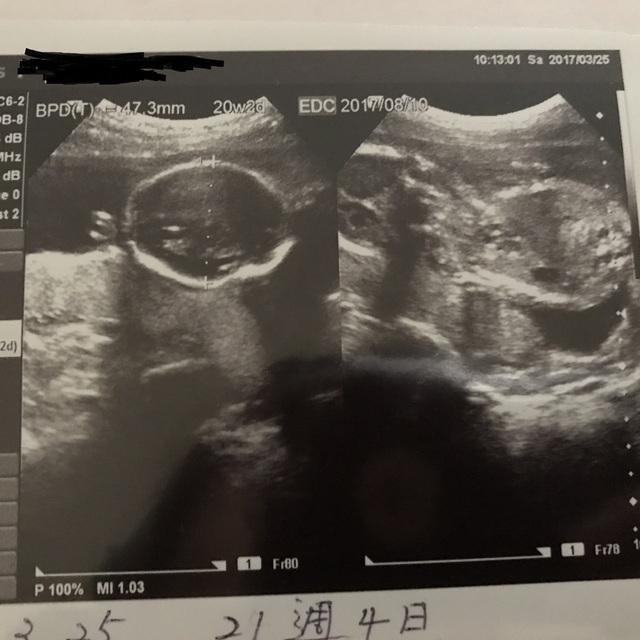

20週1日(20w1d・性別不明)|たらち さん(33歳)

エコー写真撮影時のエピソード:

旦那さんが初めて立ち会ったエコーで、かわいい姿や性別が分かるドキドキの瞬間でしたが、断面図のエコーが主だったようで、ガイコツ風のリアルな画像しか見れず、性別も分からずで、残念でした。。。

旦那さんの感想は怖いの一言でした(苦笑)